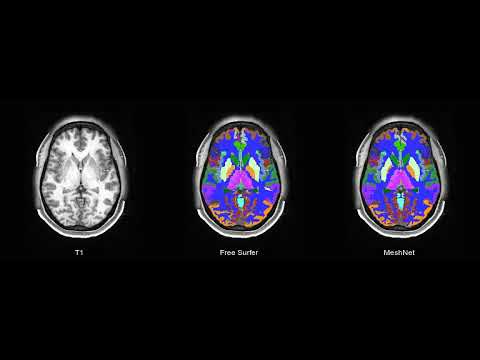

This repository contains a PyTorch implementation of MeshNet architecture. MeshNet is a volumetric convolutional neural network for image segmentation (focused on brain imaging application) based on dilated kernels [1].

This code provides a framework for training and evaluating a model for segmentation of a T1 (+ optional T2) into a 104 class brain atlas. It is a modification of our previous work [3].

Brain Atlas segmentation with brainchop.org

To get brain atlas segmentation ([3]) you don't need to run any code. Just sign up at brainchop.org, upload your 3T MRI T1 image and get brain atlas in 1-2 minutes.

Watch video with example of brain atlas segmentation.

| T1 MRI | FreeSurfer | MeshNet |